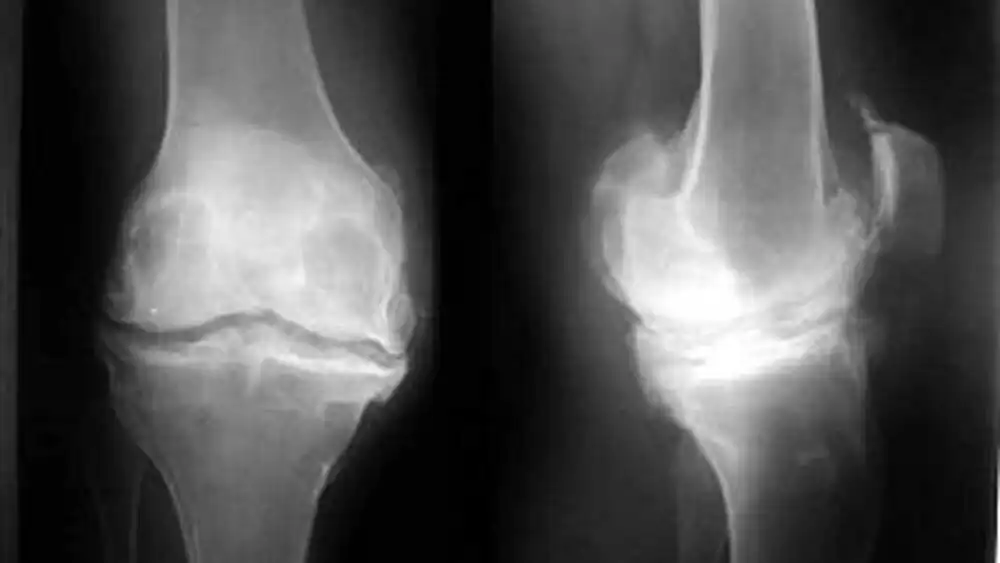

تشخیص استئوفیت زانو

تشخیص استئوفیت زانو معمولا با معاینه فیزیکی توسط پزشک ارتوپد و بررسی شرح حال بیمار آغاز می شود. پزشک متخصص با پرسیدن سوالاتی در مورد سابقه پزشکی بیمار، علائم و شدت آنها، و هر گونه آسیب یا جراحی قبلی در ناحیه زانو، اطلاعات لازم را برای تشخیص جمع آوری می کند.

در ادامه، معاینه فیزیکی زانو انجام می شود. پزشک ارتوپد به دنبال علائمی مانند درد، تورم، حساسیت به لمس، محدودیت دامنه حرکتی و صداهای ساییدگی در مفصل زانو خواهد بود.

همچنین، برای تایید تشخیص و بررسی دقیق تر مفصل زانو، ممکن است از روش های تصویربرداری زیر استفاده شود:

- رادیوگرافی (X-ray): رادیوگرافی ساده زانو می تواند وجود استئوفیت را به خوبی نشان دهد.

- MRI (تصویربرداری رزونانس مغناطیسی): ام آر آی تصویری دقیق از استخوان ها، غضروف، رباط ها و تاندون های اطراف مفصل زانو ارائه می دهد و می تواند به تشخیص سایر مشکلات احتمالی مفصل زانو مانند پارگی منیسک کمک کند.